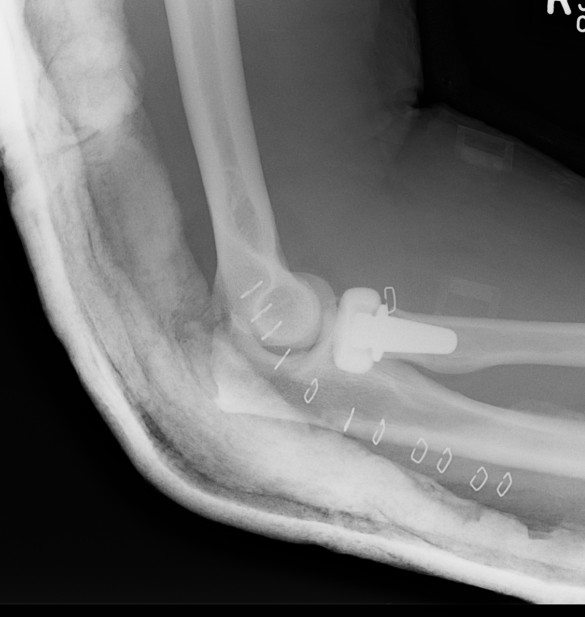

Radial Head Arthroplasty (RHA)

Design

Cobalt chrome / pyrocarbon / titanium

Modular - various head diameter / thickness + various stem sizes + collars to build up radial neck if required

Fixation - press fit v loose fit

Technique Modular Titanium Radial Head Arthroplasty

Overstuffing

| Lesser sigmoid notch | Symmetry of ulnohumeral joint |

|---|---|

|

Radial head shoulder articulate with lesser notch

Ensure no gapping of lateral ulnohumeral joint |

- cadaveric study

- increased medial ulno-humeral joint line gapping with overlengthening of 6 or 8 mm

- increased lateral ulno-humeral joint line gapping with overlengthening of 2 mm

Complications

Stiffness

Over lengthening / over stuffing

Heterotopic ossification

Pain - malposition / loosening / infection / radiocapitellar OA

Instability - associated Coronoid / LCL / MCL injuries

Radial arthroplasty malposition

Infection